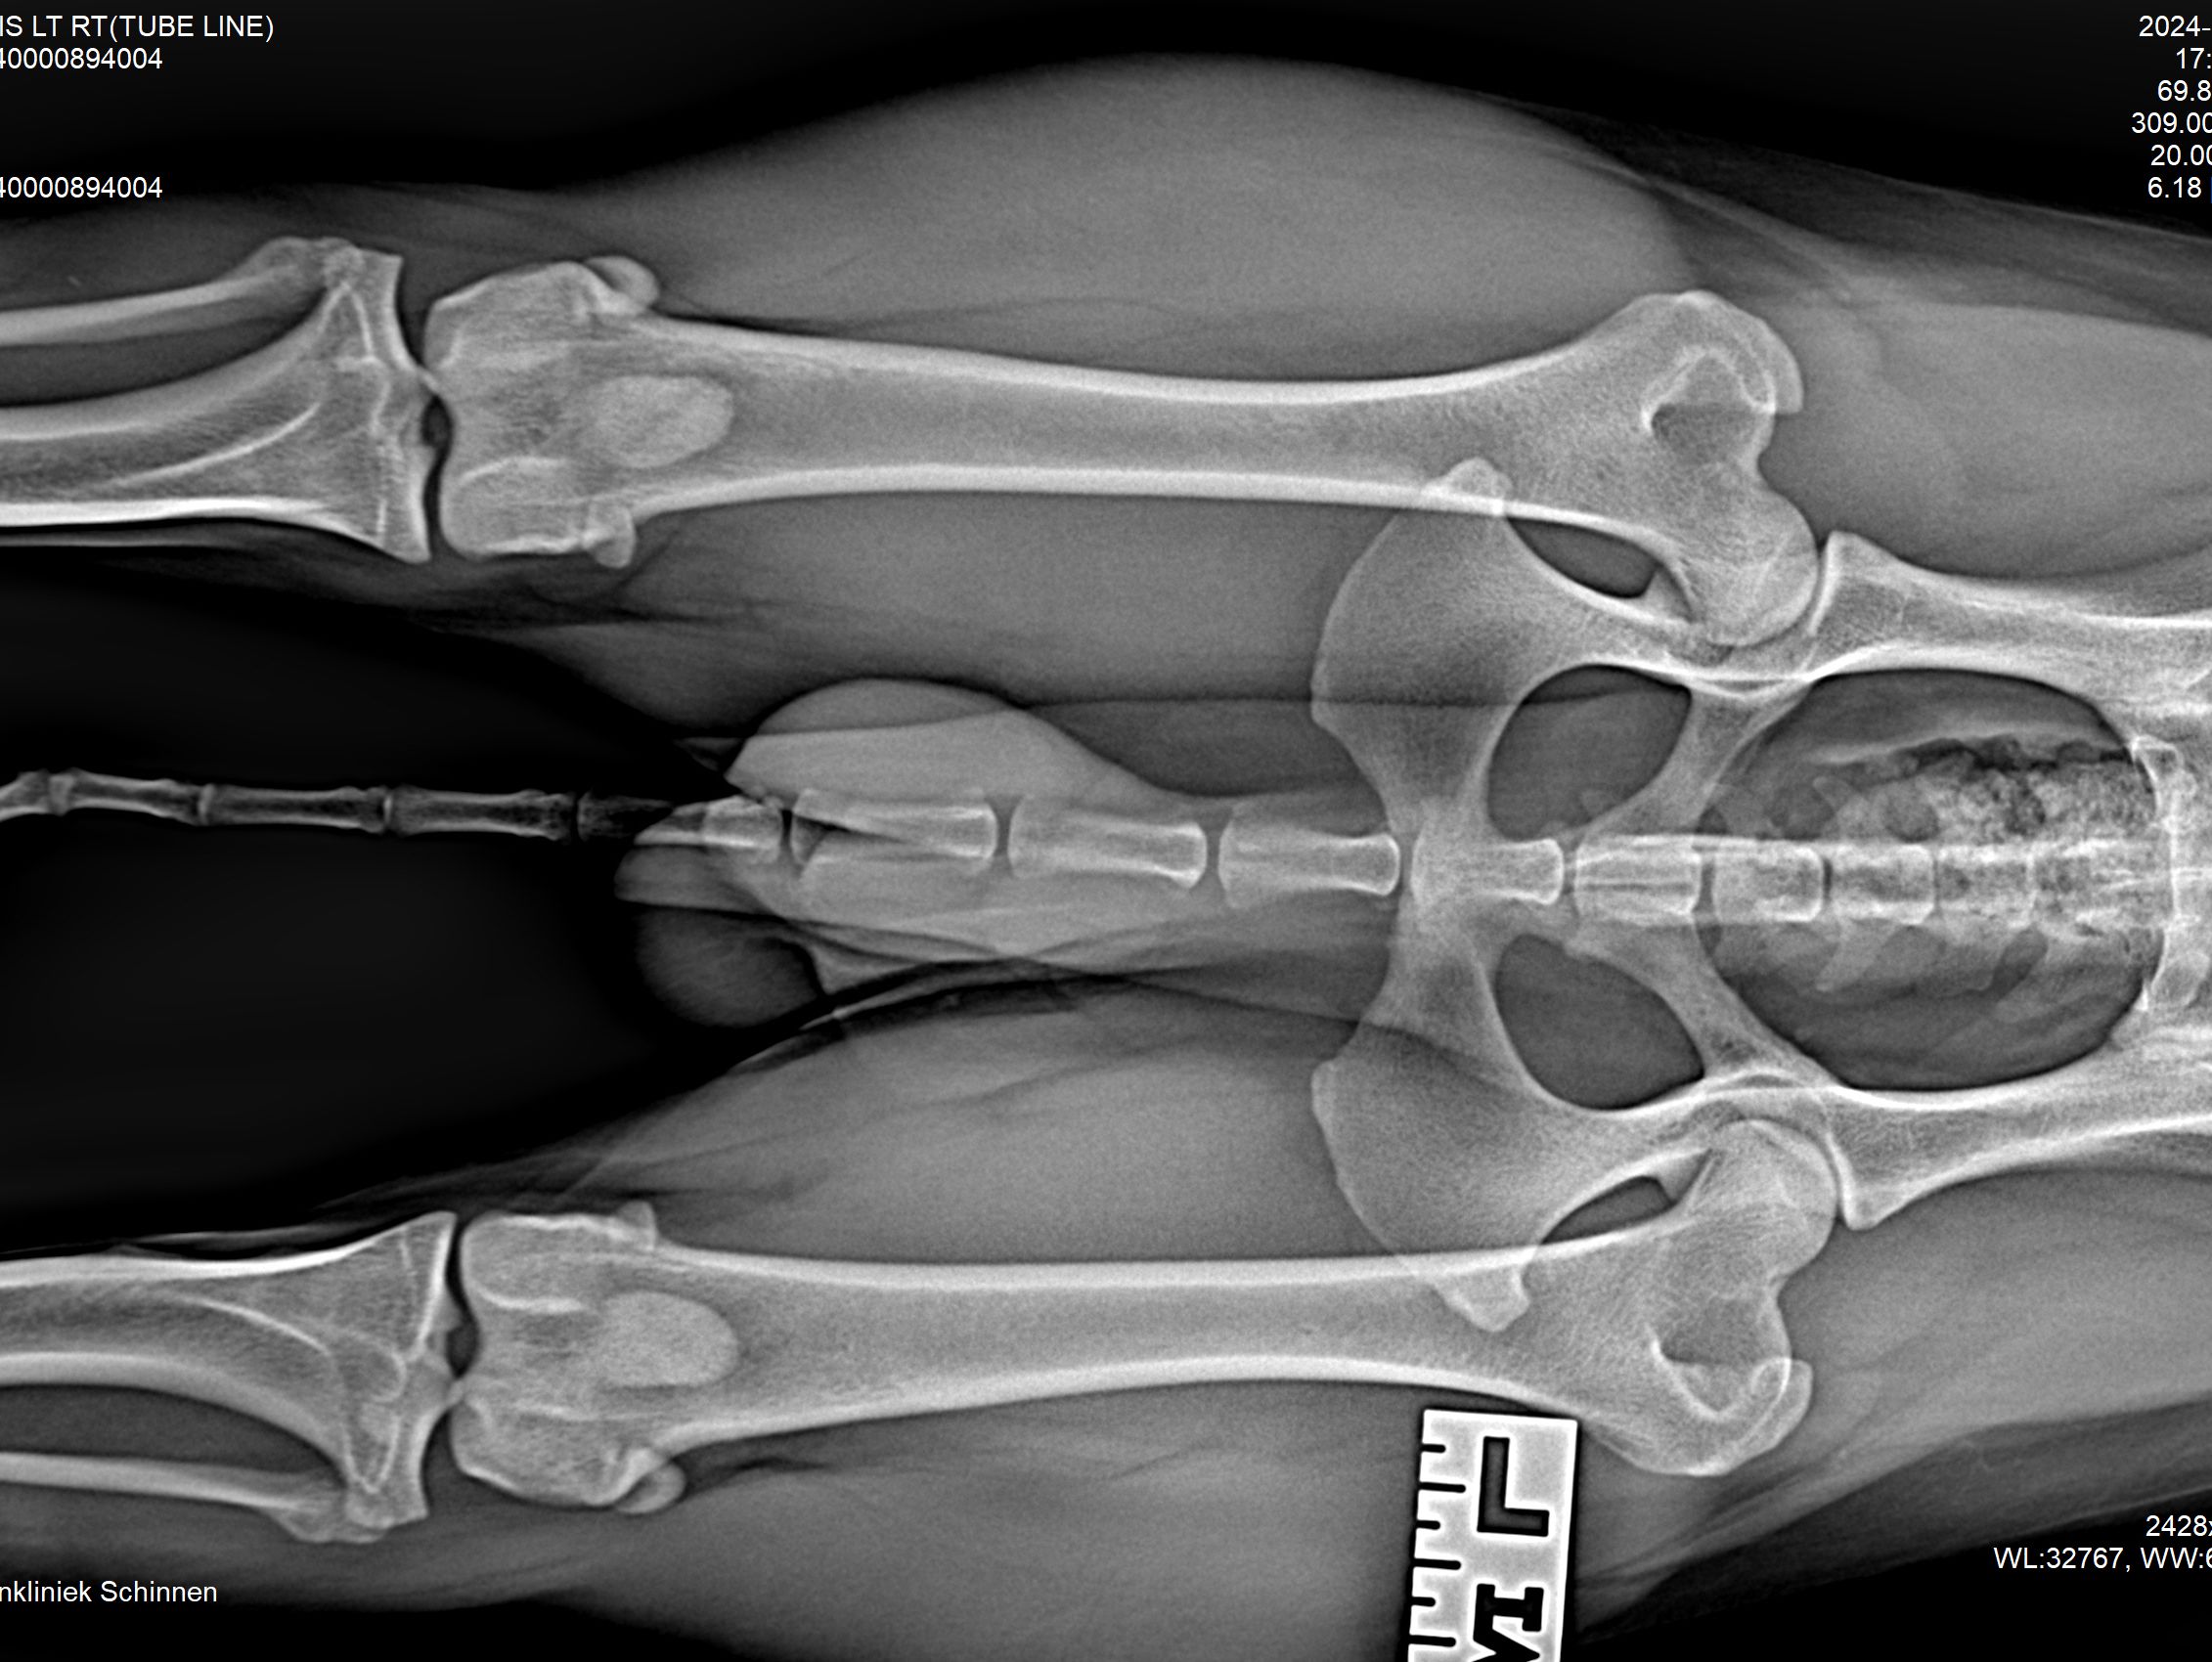

Hieronder foto's van Guus genomen met onze nieuwe DRgem rontgen. Beoordeeld met de hoogste score door de Raad van Beheer op Kynologisch gebied

Heupdysplasie onderzoek

Heupdysplasie is een ontwikkelingsstoornis van de heupgewrichten, deze aandoening kan erfelijk zijn, maar omgevingsfactoren spelen soms ook een rol. Een hond hoeft geen last te hebben van HD, dus aan de buitenkant kunt u niet zien of een hond HD heeft. Als uw hond goed kan lopen, wil dit niet zeggen dat er geen HD speelt. Om dit met zekerheid te kunnen beoordelen zijn röntgenfoto’s van de heupen nodig.

Meestal passen wij een sedatie toe bij het maken van de officiële HD-foto’s. Dit is nodig om een kwalitatief goede foto te maken, welke aan de hoge eisen van de beoordelingscommissie moet voldoen. Uw hond moet op zijn of haar rug liggen, waarbij het bekken en de achterpoten symmetrisch worden gestrekt en de knieschijven moeten op juiste manier worden ingedraaid.